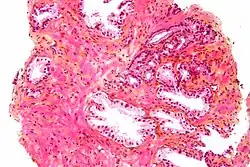

Microfotografia de glândulas prostáticas benignas com corpos amiláceos. Coloração H&E.

A próstata consiste em tecido glandular e conjuntivo. Células altas em forma de coluna formam o revestimento (o epitélio) das glândulas.[1] Estas formam uma camada ou podem ser pseudoestratificadas.[3] O epitélio é altamente variável e áreas de células cuboidais baixas ou planas também podem estar presentes, com epitélio transicional nas regiões externas dos ductos mais longos.[9] As glândulas são formadas como muitos folículos, que drenam para os canais e, subsequentemente, para 12–20 ductos principais. Estes, por sua vez, drenam para a uretra à medida que passa pela próstata.[3] Há também uma pequena quantidade de células planas, que ficam próximas às membranas basais das glândulas e agem como células-tronco.[1]

O tecido conjuntivo da próstata é composto de tecido fibroso e músculo liso. O tecido fibroso separa a glândula em lóbulos.[1] Ele também fica entre as glândulas e é composto por feixes de músculos lisos orientados aleatoriamente que são contínuos com a bexiga.[10] Com o tempo, secreções espessadas chamadas corpora amylacea se acumulam na glândula.[1]